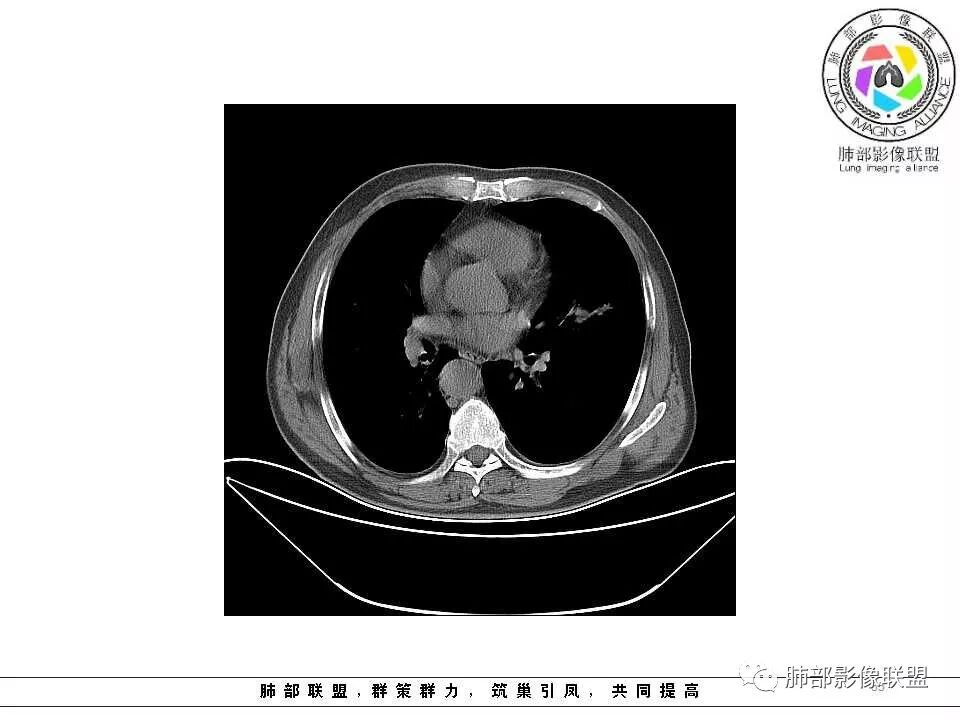

老年男性,左肺舌段见多个小结节灶及斑片状高密度灶、磨玻璃影,结节灶边界清晰,光滑,无明显分叶,密度均匀,周围病灶密度不均,一年内生长,考虑恶性肿瘤并阻塞性肺炎出血,小细胞可能大。

老年男性,肺气肿背景,左肺上叶舌段结节明显增大,边缘膨隆,有磨玻璃结节,与血管联系紧密,周围可见条片影,首先考虑恶性肿瘤,鳞癌伴阻塞性炎症,鉴别炎性

老年男性,吸烟,坐上肺结节增大,气管可见堵塞,周围GGO边界清楚,考虑恶性,倍增时间小细胞不符合,考虑鳞癌或腺癌

老年男性,以咯血为主要表现,CT左肺舌段结节影,实性,边缘清楚锐利,部分膨胀,周围磨玻璃结节及树芽征,周围有空气潴留,首先考虑占位,鉴别结核。

肺气肿背景,左肺上舌叶结节一年复查明显增大,边缘光滑。下舌叶片状影,界限模糊。考虑上舌叶小细胞癌并下舌叶感染。鉴别鳞癌

左肺上叶舌段见前后两个小结节,边缘清晰,无分叶毛刺,前方小结节见小气管穿行,临近血管纹理无牵拉,结节下方层面见条片状密度增高影,局部纹理增强,边缘模糊,内见气管影,上肺上叶见多个小透光区,纵膈内见增大小淋巴结影,考虑1·良性改变,炎性可能,2·肺气肿。病变短期变化明显,肿瘤不考虑,结节与舌段肺炎关系不大

老年男性,肺气肿背景,对比前片,左肺上叶舌段结节较前进展,周围有斑片状条状密度增高影,左肺门淋巴结肿大,有咯血史抗炎后效果不佳,目测增强强化不好判断,考虑肺癌并阻塞性肺炎可能,鉴别炎症性肺癌,真菌类肺炎,肺脓肿,肺结核,建议完善肿瘤标志物,结核相关检查,病原体检查。

老年男性,咯血一个月,有慢支病史。左肺上叶舌段可见一类圆形结节影,边缘光滑,远端有片条状影,一年前胸ct基本正常。感觉还是考虑肺癌合并阻塞性炎症。鳞癌还是小细胞?